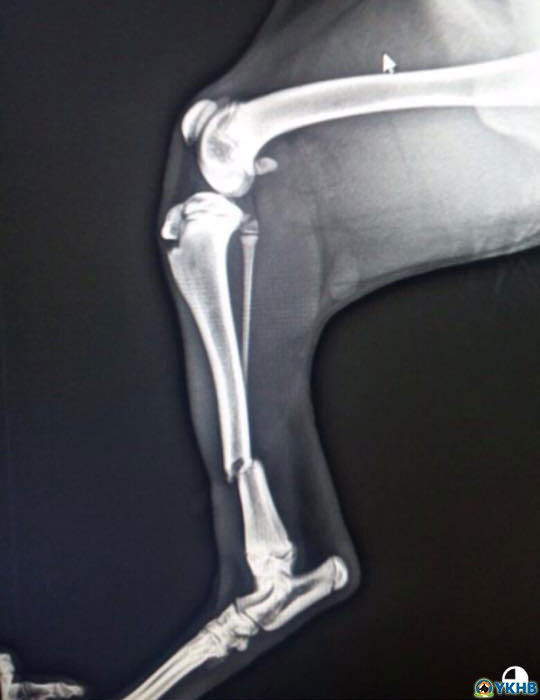

Yaralılar için destek

Hangi birinin ilanını yapayım o kadar çok trafik kazası yaralı , şiddet görmüş, tekmelenmiş , üzerine yakıcı sıvı dökülmüş  hayvan geliyor ki ilan yapmaya bile vakit bulamıyorum. Tek vakit bulunduğum şey hemen kliniğe yollamak ve tedavilerini yaptırmak. Allaha şükür tedaviye tanıt verip iyileşen çok çok fazla. Kayıplar tabii ki oluyor ama kaderine bırakmayıp borç harç tedavi ettiriyoruz. Klinikte kara kaplı borç defteri iyice şişti. Bu gün artık derdimi anlatma zamanı geldi diye düşündüm.

Dertler paylaştıkça azalır. Ameliyat olan hastalar için ilave olarak ameliyat MASRAFLARI üzerine bir de pansiyon parası ödememek için ilaç tedavisine barınakta devam ediyoruz o nedenle de ilaçlara da ihtiyacımız oluyor. Ben dikkatinizi çekti ise ender olarak destek isterim çok zorda kaldığım da. Ancak, bugünler de o zor zamanlarımız. Sizlerden destek bekliyoruz ilaç olabilir ameliyat masraflarıma sponsor veya katkı olabilir.